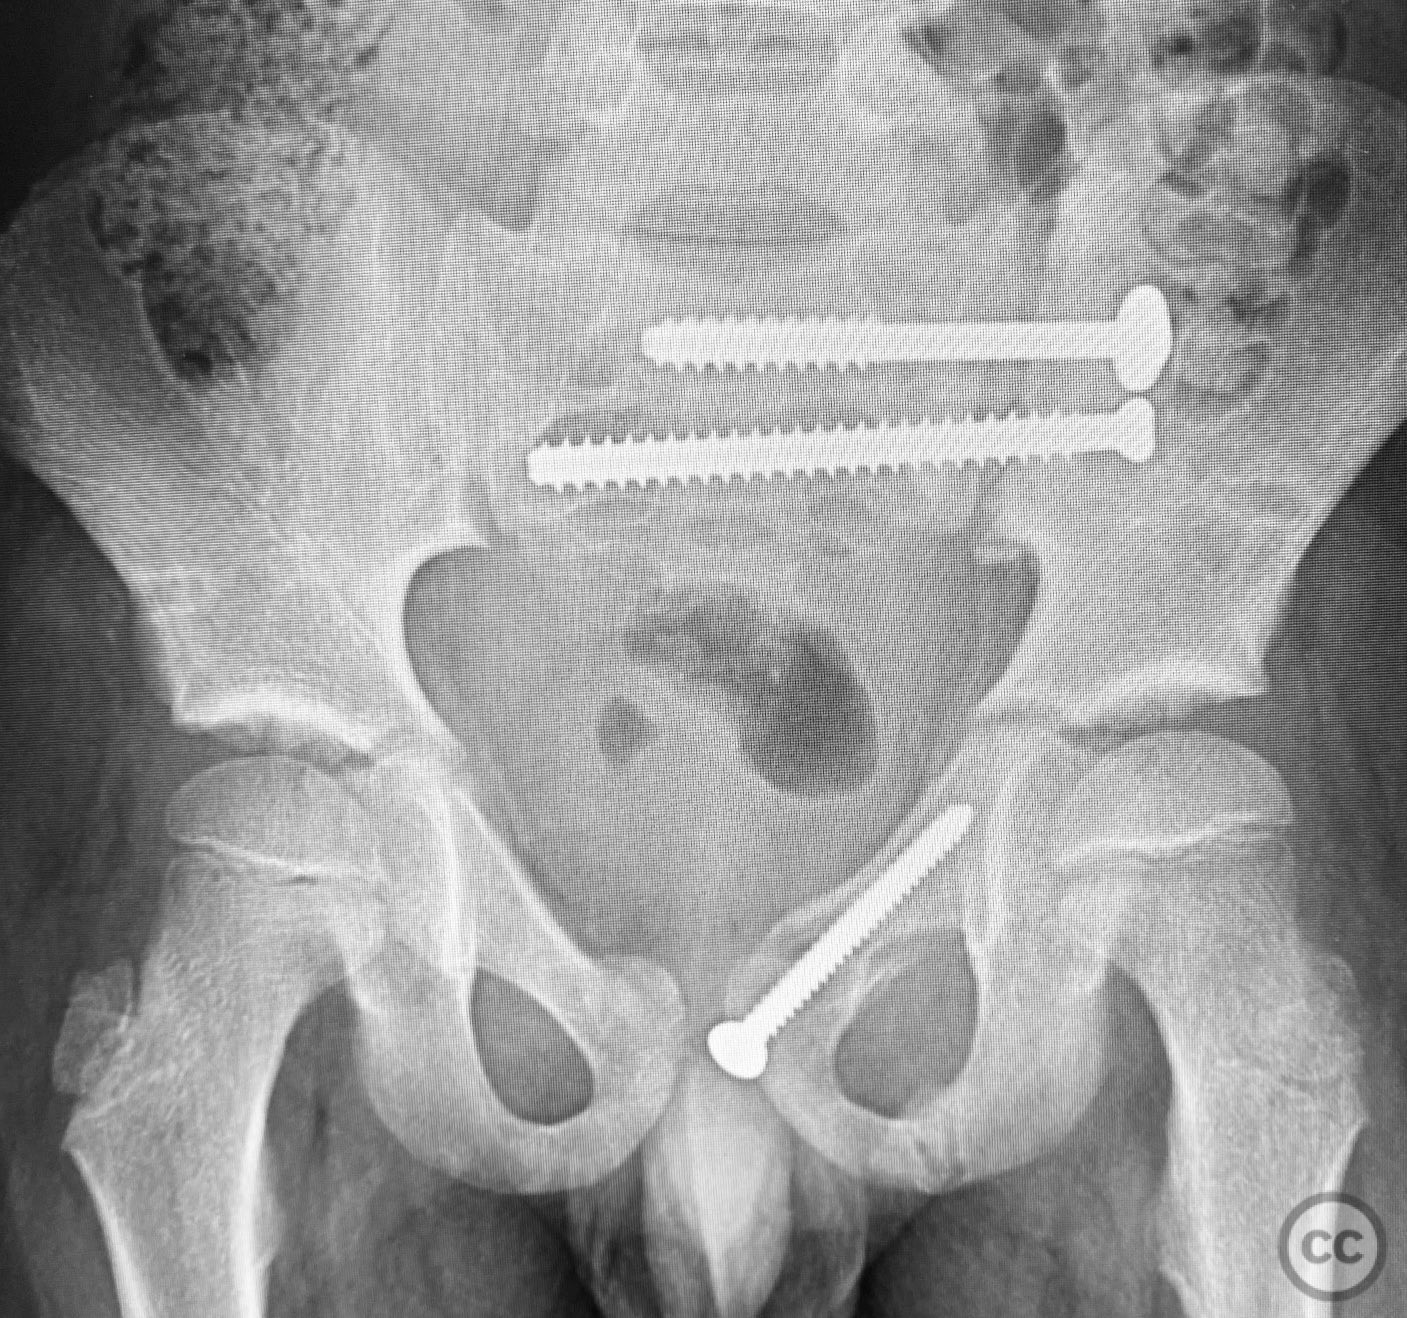

Closed reduction was achieved under fluoroscopic guidance, with satisfactory alignment of both anterior and posterior elements. A 4.5mm cortical screw was placed percutaneously across the superior pubic ramus fracture, and a 7mm cannulated cancellous screw was inserted across the posterior pelvic ring injury. No intraoperative complications were encountered. Implant removal was performed 10 months postoperatively without incident.

Orthopaedic implants used:   4.5mm cortical screw (superior pubic ramus), 7mm cannulated cancellous screw (posterior pelvic ring).